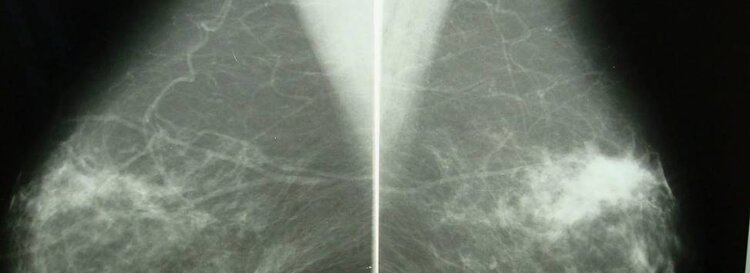

Фиброзная мастопатия молочной железы – это распространенное доброкачественное состояние, характеризующееся изменениями в ткани молочной железы.